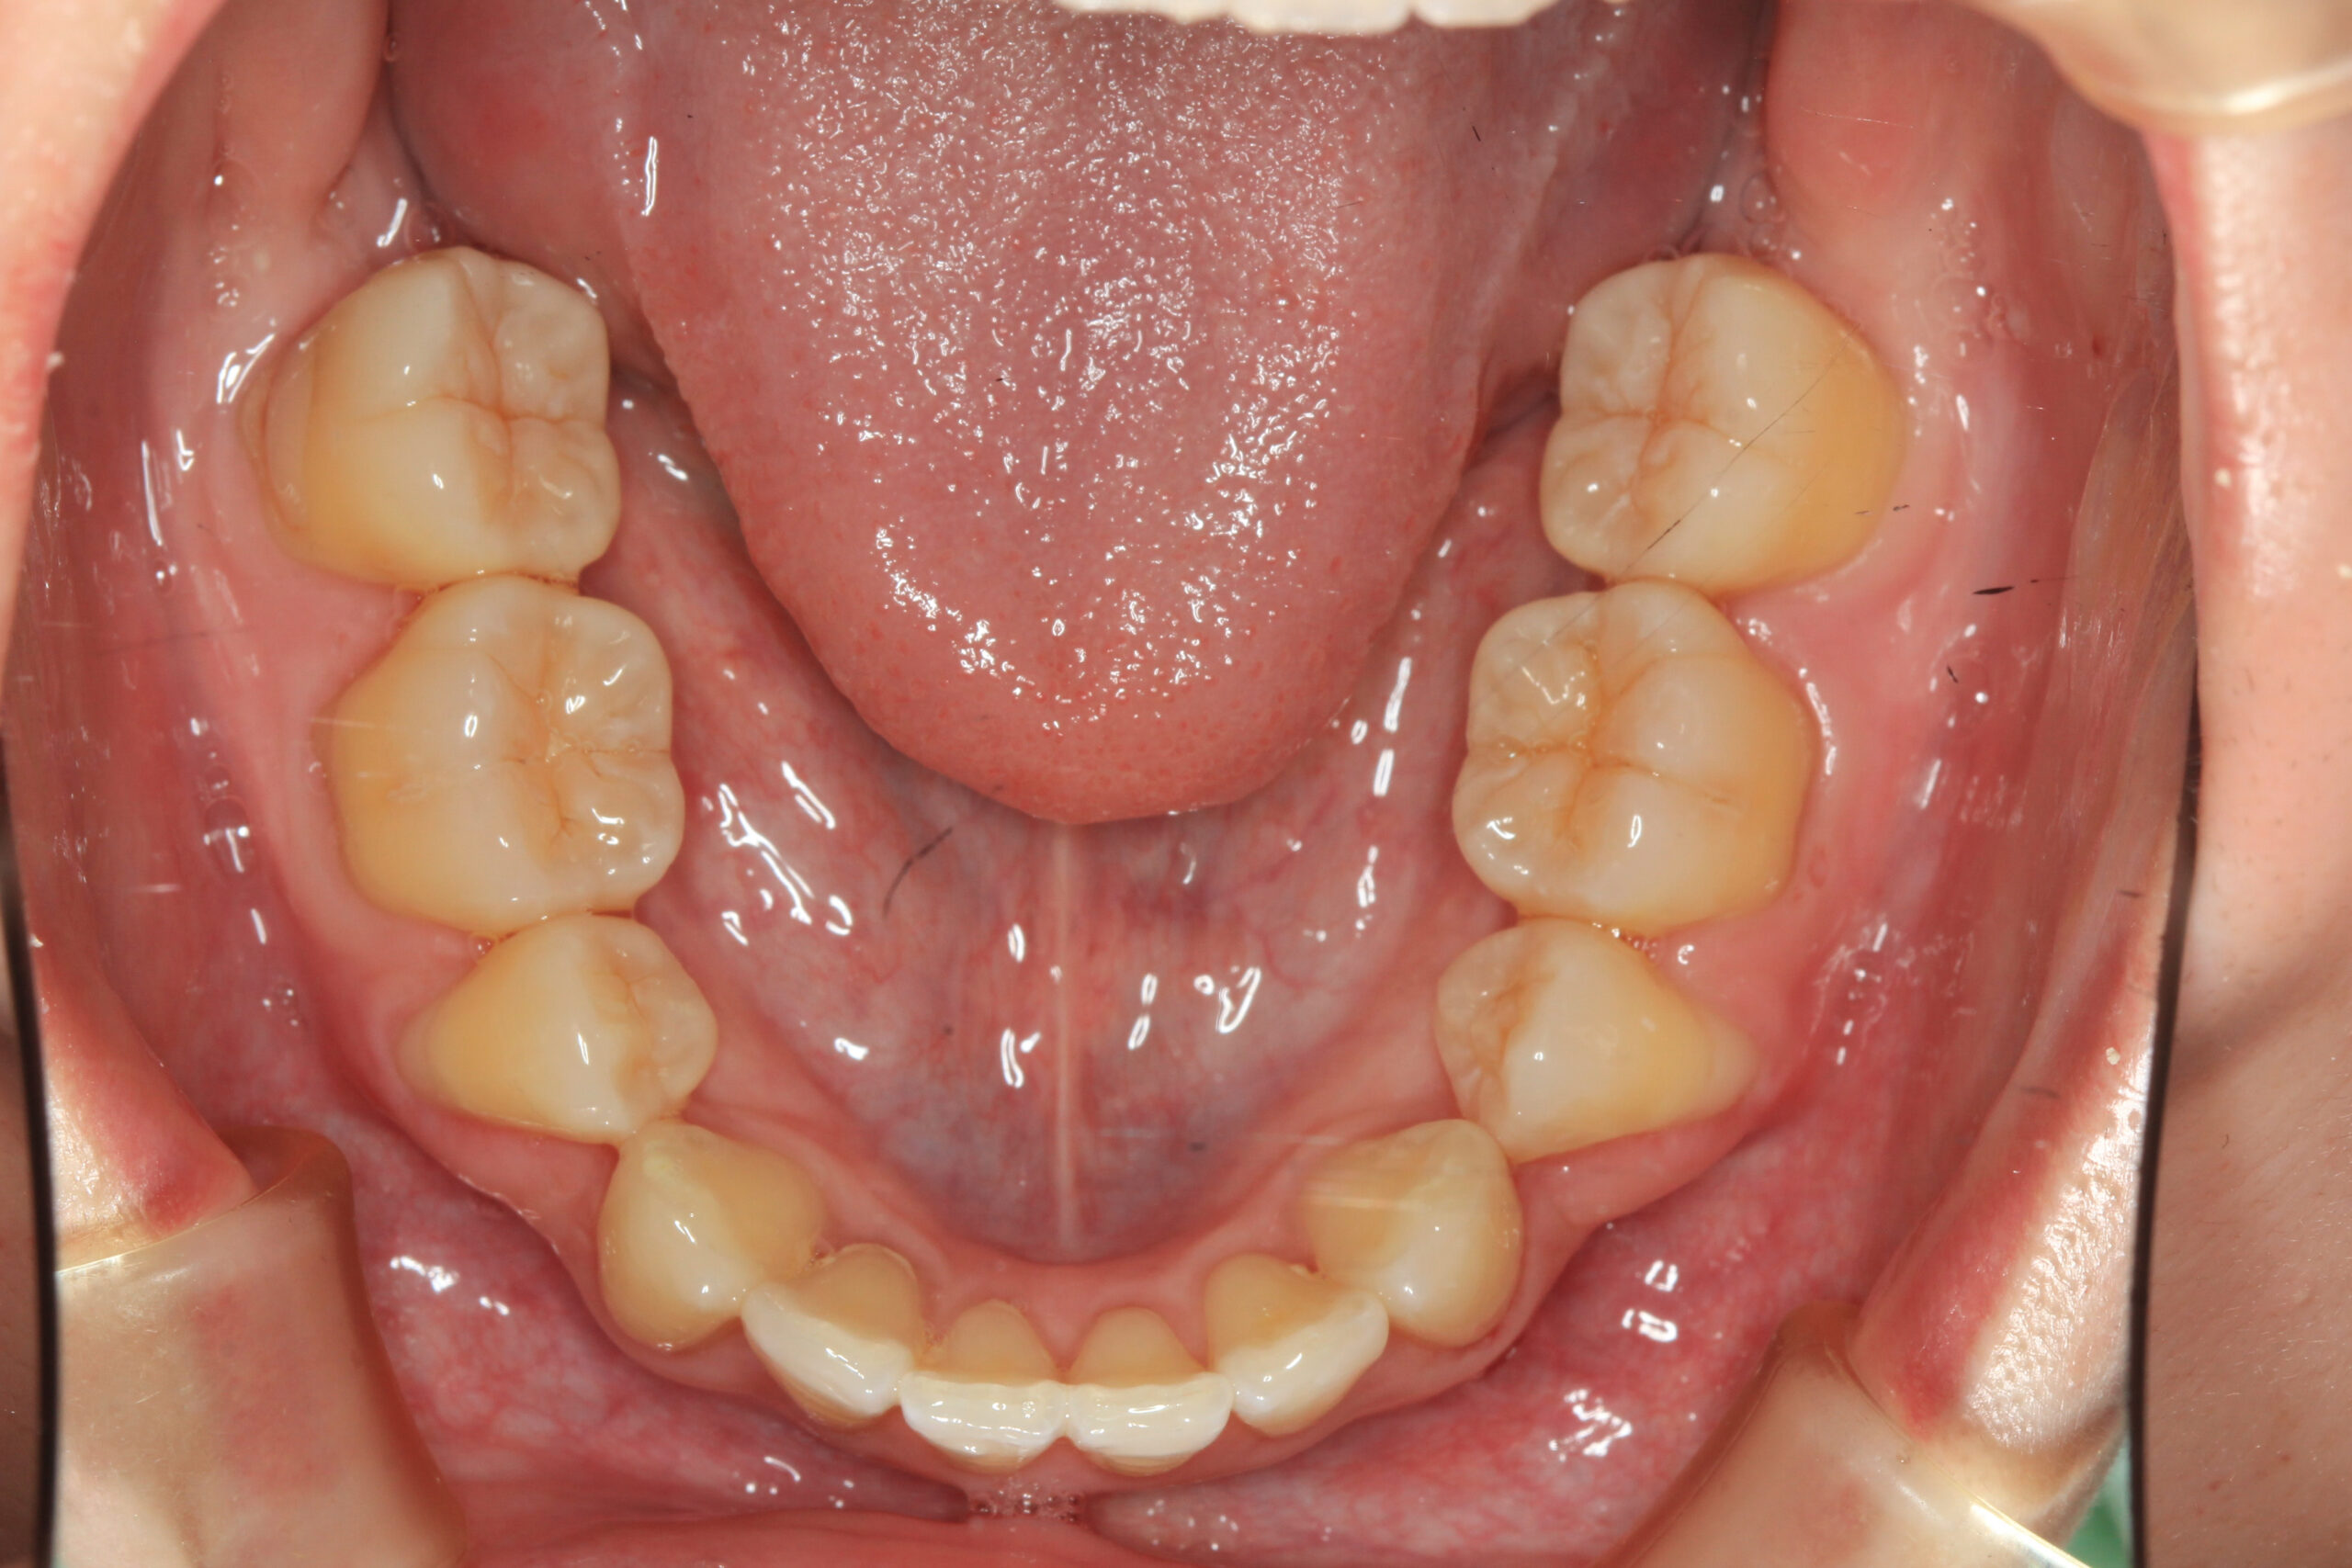

下顎も左右の小臼歯抜歯後綺麗に並んでいます。

上下左右小臼歯抜歯して前突を改善しました。 凄い綺麗に前突が改善されているのが分かります。

今回のケースは上下顎前突の症例です。

上下左右の小臼歯を抜歯して最大限に前歯を引っ込めました。